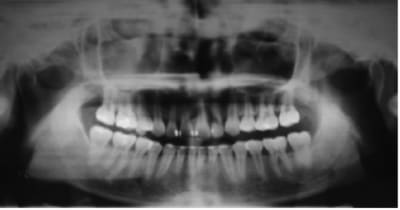

que feriez vous dans ce cas? extraire la 37 et tracter la 38 en position de la 37 ou preserver la 37 qui semble-t-il a un pronostic endodontique defavorable!

quel est le meilleur rapport benefice risque?

Quel pronostic concernant la traction d'une sagesse quasi horizontale comme sur la pano?

La question m'interpelle, je suis en général favorable aux extractions/tractions des 8, mais c'est typiquement le cas ou j'ai un doute...

Vu l'état de la denture sur la pano, il faut mieux commencer par des choses simples, puis réévaluer la motivation, avant de se lancer dans un ttt multiattaches potentiellement cariogène.